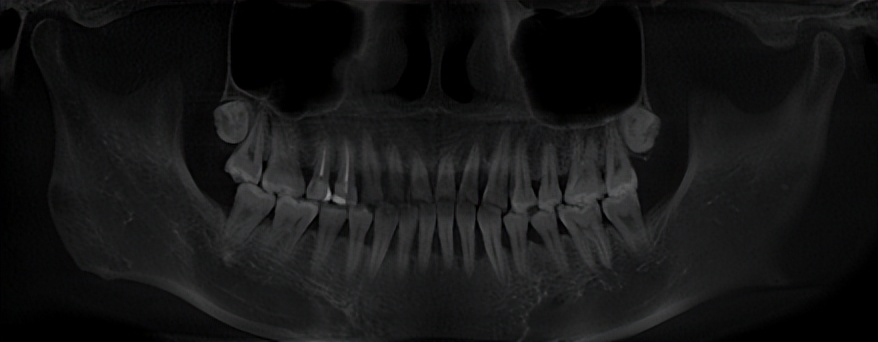

顾不上难为情,我全程超级配合医生的各种检查,把X光片、口内照片、扫描、探诊、口腔曲断全拍了一个遍,就是想知道我的牙现在“坏”到了哪种程度。医生操作非常熟练,手法也温柔,很快就检查完了。

最后的检查结果超出我的想象,检查报告显示,我有很严重的全口菌斑、软垢、色素(都是3个+),还有轻微龈上牙石和重度龈下牙石,全口牙龈充血水肿明显,伴随有脓,以及全口牙龈肿胀、全口牙槽骨吸收、3颗牙松动……简直满口都是问题。

(有两颗牙已经透光)

医生给我做了专业的诊断,说我是I期C级广泛性牙周炎+16.26.35牙近中角型吸收,病症发展比较迅速,但是积极治疗、好好清洁就能恢复。